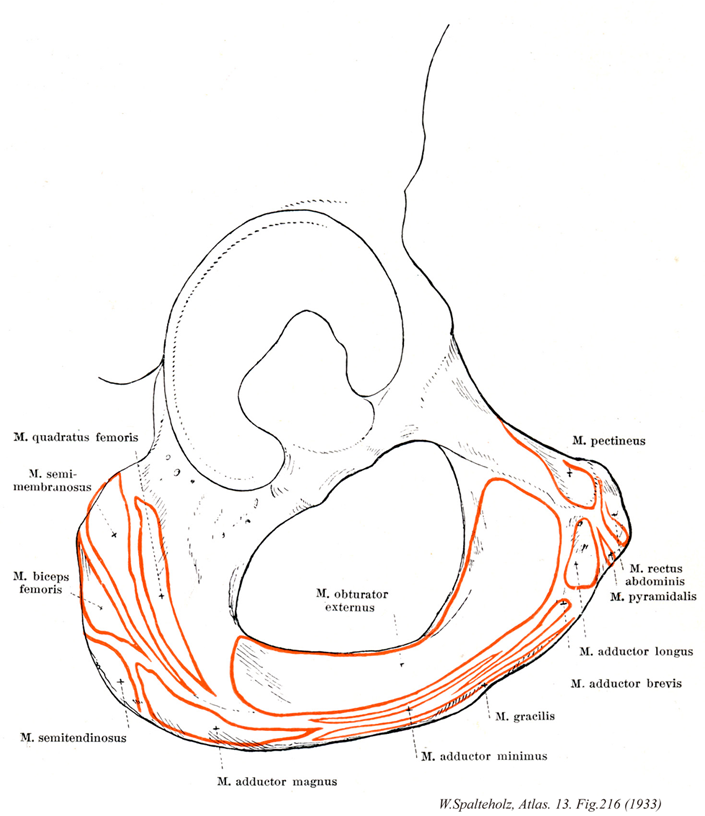

216

- 216_00【Hip bone; Coxal bone; Pelvic bone寛骨 Os coxae】 Bony structure comprising the ilium, ischium, and pubis.

- 216_01【Quadratus femoris muscle大腿方形筋 Musculus quadratus femoris】 o: Ischial tuberosity. i: Intertrochanteric crest. Lateral rotation and adduction. I: Sacral plexus.

- 216_02【Semimembranosus muscle半膜様筋 Musculus semimembranosus】 o: Ischial tuberosity. i: Medial condyle of tibia and oblique popliteal ligament. It is partly covered by the semitendinosus muscle. Extension at the hip joint; flexion and medial rotation at the knee joint. Tenses the knee joint capsule. I: Tibial nerve.

- 216_03【Biceps femoris muscle大腿二頭筋 Musculus biceps femoris】 Two-headed muscle arising from the pelvis and femur, i: Head of fibula. Flexion at the knee joint, lateral rotation.

- 216_04【Semitendinosus muscle半腱様筋 Musculus semitendinosus】 o: Ischial tuberosity. i: Medial surface of tibia. Extension at the hip joint. Flexion and medial rotation at the knee joint. I: Tibial nerve.

- 216_05【Pectineus muscle恥骨筋 Musculus pectineus】 o: Pectineal line of pubis. i: Pectineal line of femur, linea aspera. Flexion, adduction, and medial rotation at the hip. I: Femoral and obturator nerves.

- 216_06【Rectus abdominis muscle腹直筋 Musculus rectus abdominis】 o: Fifth to seventh costal cartilages, xiphoid process, i: Pubic crest and pubic symphysis. Anterior flexion of the trunk, lowering of the thorax, and elevation of the pelvis. 1: Thoracic nerves T7-T12.

- 216_07【Pyramidalis muscle錐体筋 Musculus pyramidalis】 Muscle located between two layers in the anterior part of the rectus sheath. o:Pubic crest and pubic symphysis. i: Linea alba. I: Subcostal nerve.

- 216_08【Adductor longus muscle長内転筋 Musculus adductor longus】 o: Near the pubic symphysis. i: Medial lip of linea aspera. Adduction, lateral rotation, and flexion at the hip joint. I: Obturator nerve.

- 216_09【Adductor brevis muscle短内転筋 Musculus adductor brevis】 o: Inferior pubic ramus. i: Medial lip of linea aspera. Adduction, flexion, extension, and lateral rotation at the hip. I: Obturator nerve.

- 216_10【Gracilis muscle薄筋;大腿薄筋 Musculus gracilis】 o: Inferior pubic ramus. i: Medial tibial surface. Adduction, flexion, and extension at the hip joint. Flexion and medial rotation at the knee joint I: Obturator nerve.

- 216_11【Adductor minimus muscle小内転筋 Musculus adductor minimus】 Superior portion of the adductor magnus, taking origin further to anterior from the pelvis.

- 216_12【Adductor magnus muscle大内転筋 Musculus adductor magnus】 o: Inferior pubic ramus, ramus of ischium. i: Medial lip of linea aspera and, via a long tendon, the medial epicondyle. Adduction, lateral rotation, and extension at the hip joint. I: Obturator and tibial nerves.